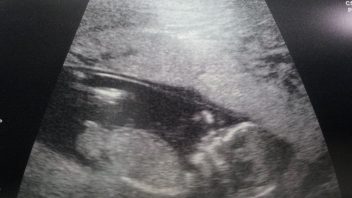

KLUB TĚHULEK! IVA Už to mám potvrzené. Od 8.10. jsem oficiálně na mateřské dovolené. Zvláštní pocit. Ne, že by se něco po téměř měsíci, co jsem doma, změnilo, ale ten pocit je jiný. To víte, se svým prvním těhotenstvím, na které jsme si tři roky počkali, prožívám úplně všechno.

Iva právě prožila 35. týden těhotenství. Chcete vědět, co se v tomto týdnu děje s vaším tělem?